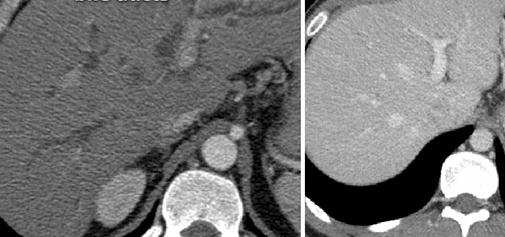

Компьютерная томография демонстрирует поликистоз почек и печени

КТ в разных проекциях показывает опухоль в левой почке (стрелка)

Органы брюшной полости, ретроперитонеального пространства. КТ живота является точным методом для диагностики абдоминальных патологий:

опухолей (КТ показывает стадию и распространенность рака, ответ на лечение).